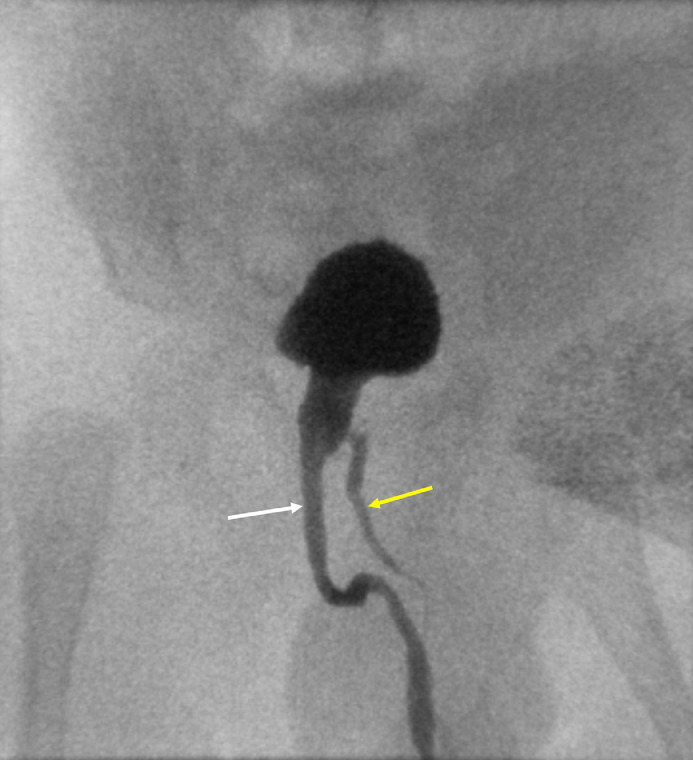

Vesicocystourethrogram (Fig. 4) demonstrates normal flow during voiding phase in the well-developed right penile urethra. The left penile urethra was relatively smaller in caliber (but patent) and proximally it terminated in the right prostatic urethra. The imaging findings were consistent with true partial diphallia.

Fig. 4.

Voiding phase of the vesicocystourethrogram demonstrates a well-developed urethra of the right penile shaft (white arrow). The left penile urethra is relatively smaller in caliber (but patent), which proximally terminates to the main prostatic urethra (yellow arrow).